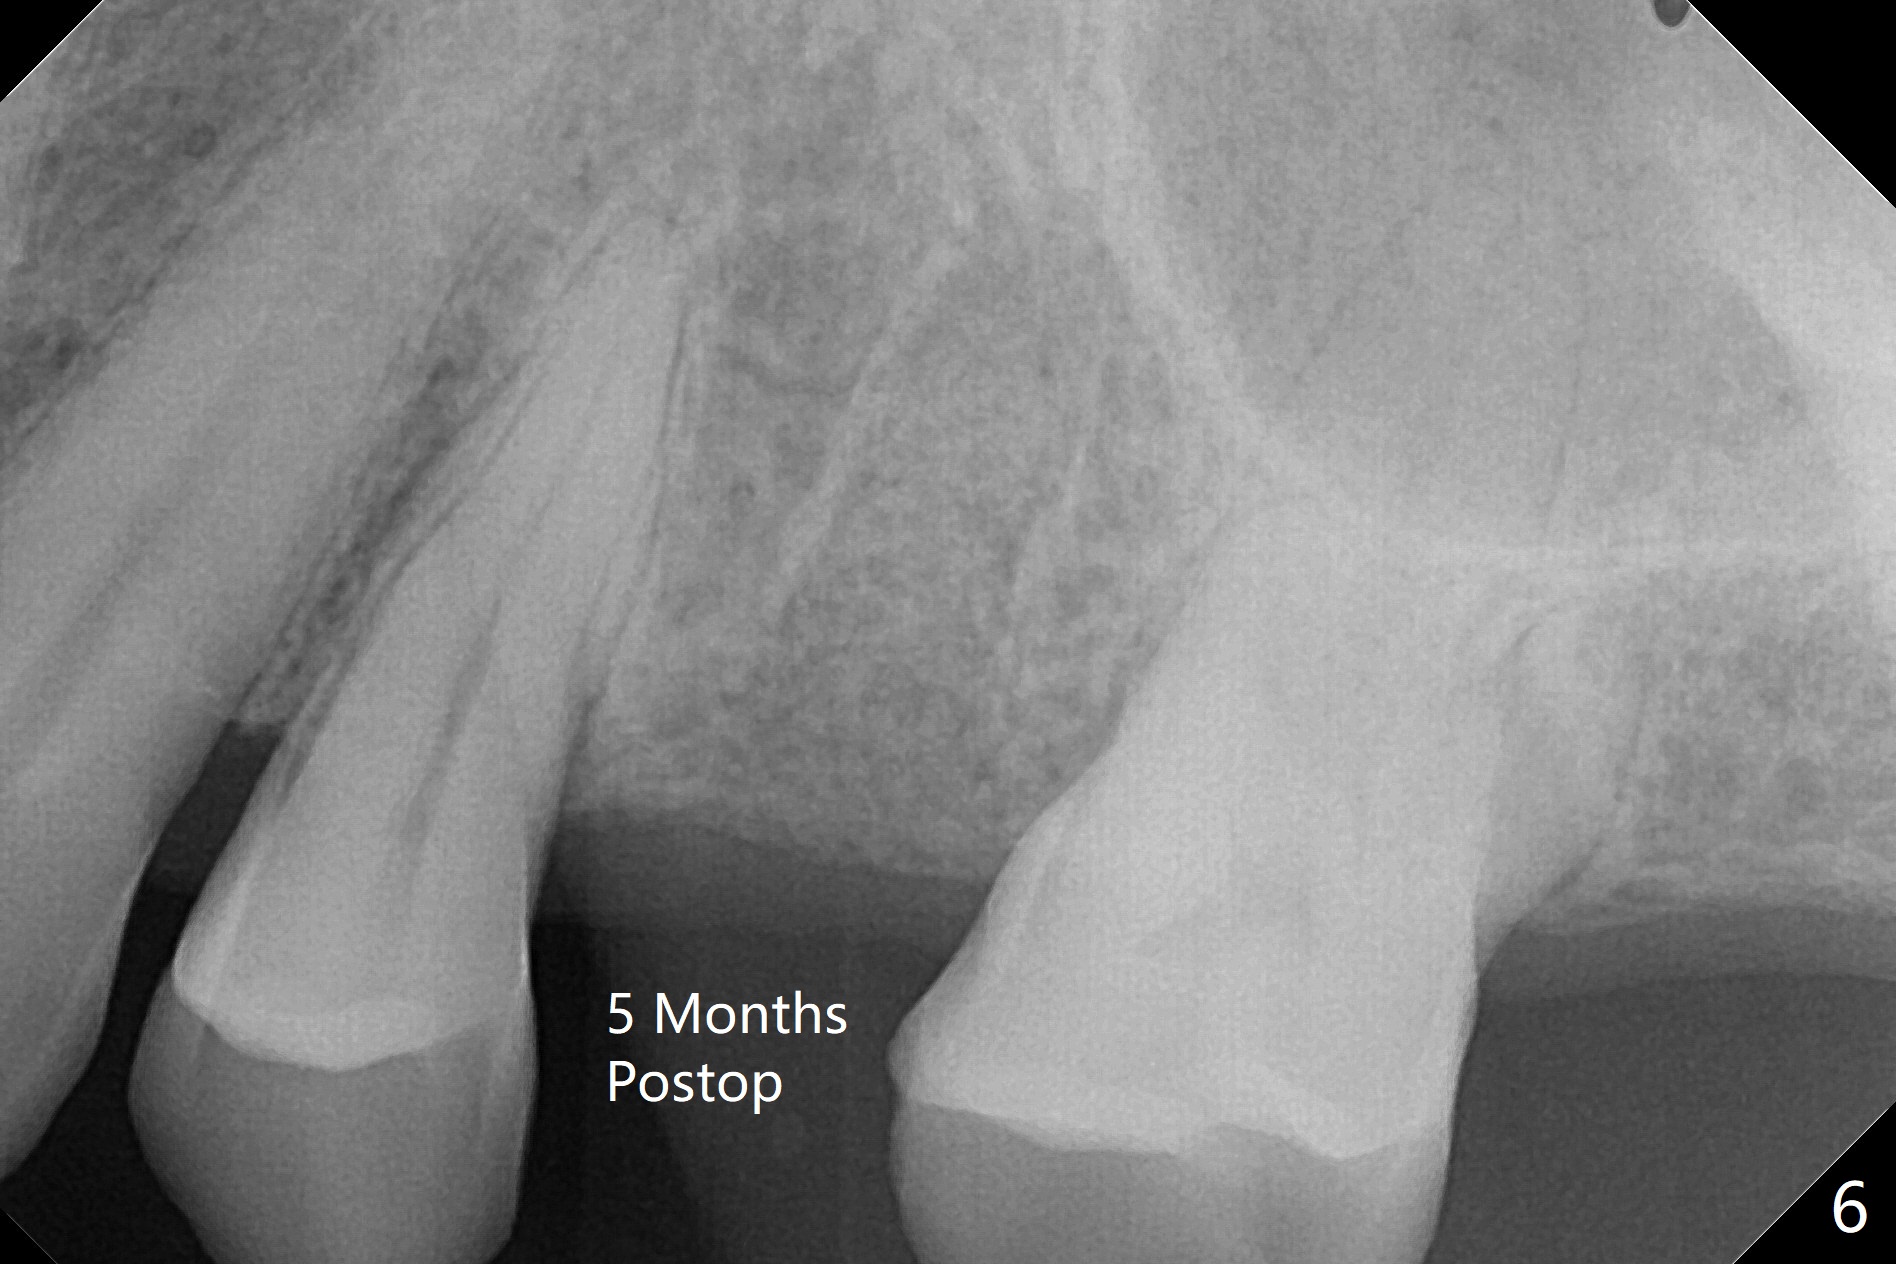

A 65-year-old man cracks 3 teeth in ~2 years (Fig.1,2 (#4,13,15)). The tooth #4 is symptomatic after RCT (Fig.1); it appears that the buccal canal is incompletely filled (data not shown). In fact an exam 1 month later shows that the symptomatic tooth is #2 (crack), while #4 is salvageable (Fig.8). The tooth #13 has palatal subgingival fracture with severe pain (Fig.2 with palatal defect). In fact the title of this case is incorrect). After extraction, allograft is placed (Fig.3 *) with 6-month membrane. In fact the bone graft is not packed into the apex of the socket; a condenser should have been used. The patient returns 3 days postop before leaving abroad. The 6-month membrane remains in place (Fig.4), while the ridge at #15 is minimally atrophic (Fig.5). The coronal lamina dura becomes indistinct 5 months postop (Fig.6). The bone graft remains in the socket. The distoapical portion of a 4x11.5 mm implant may be in the sinus (Fig.7).